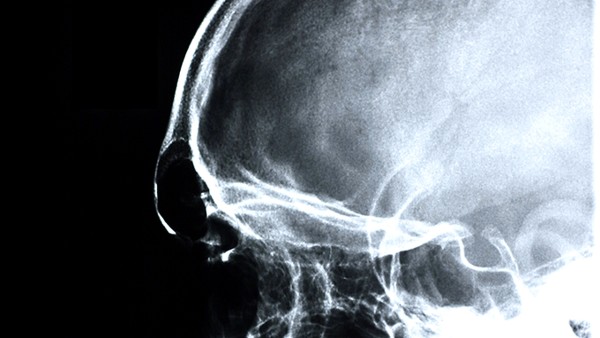

检查小脑萎缩、失神发作半年了,建议及时就医治疗。小脑萎缩是一种神经影像学表现,常见于老年人,由于年龄增长导致脑组织体积缩小而引起的一种疾病。